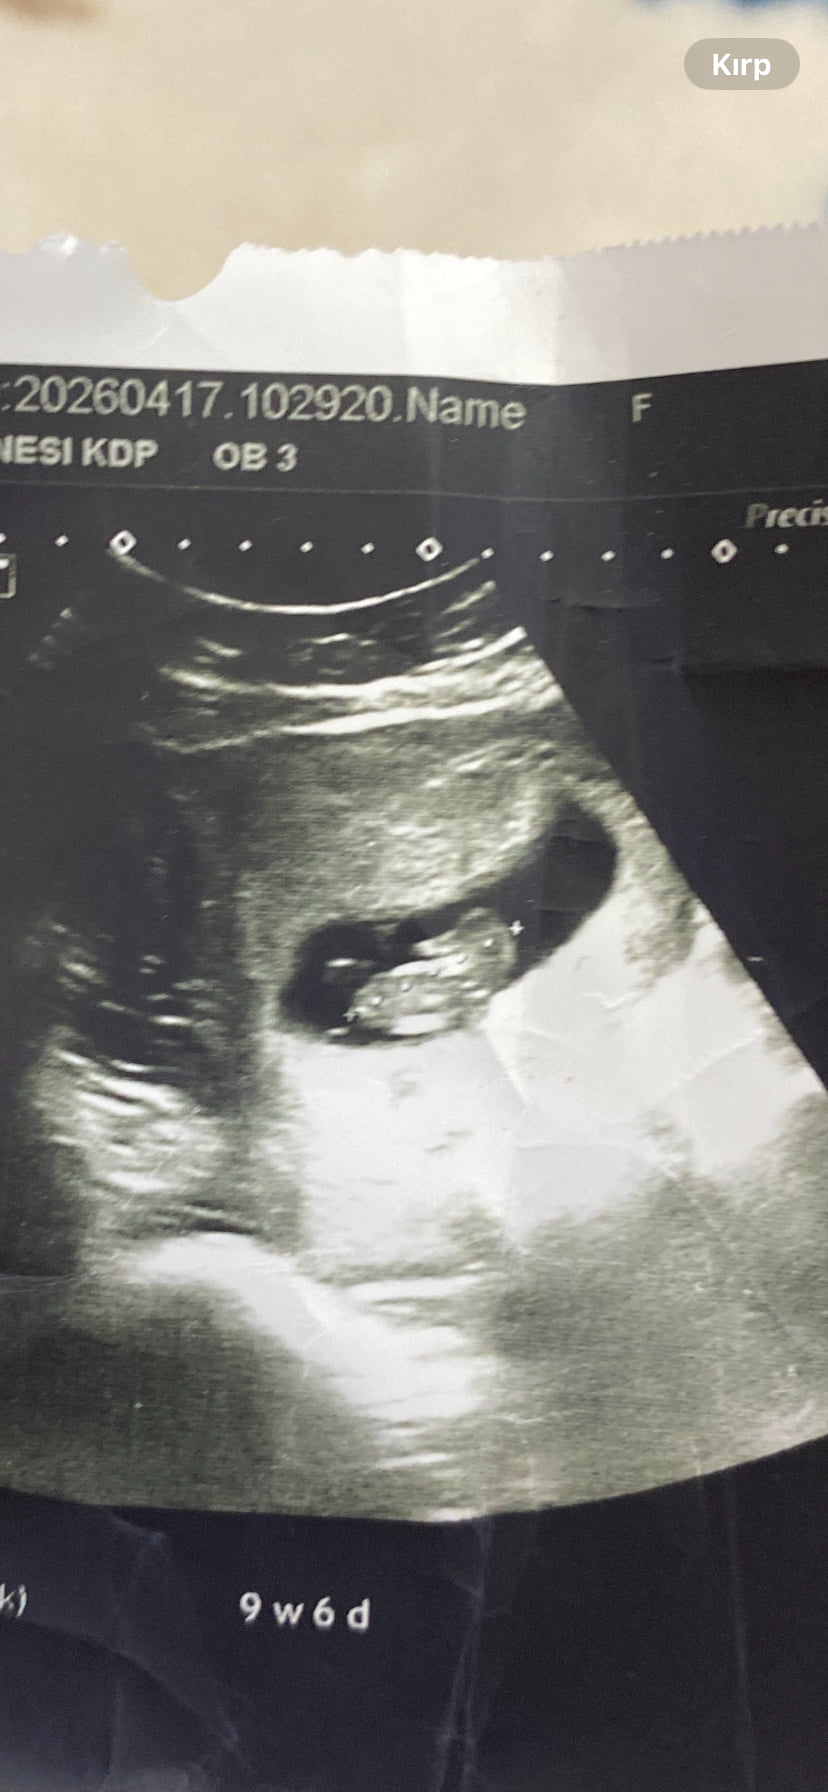

Erkek olması yüksek bence

Erkek bence

Bence kız mercimek gibi olursa kız derler fasulye gibi olurs erkek derler hakkında hayırlısı olsun canım